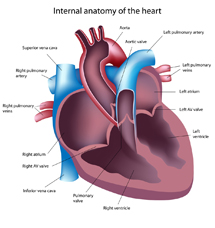

The heart is a muscular organ that pumps blood to the body. Oxygen and nutrients that are required to fuel the pump are carried to the heart in the coronary arteries. The most common cause of coronary artery narrowing is atherosclerosis where fatty deposits (plaques) build up within the coronary arteries.

The heart pumps blood to your body and the lungs. It has four chambers that are separated by valves (mitral and tricuspid valve) which ensures blood flows around the heart in the right direction. The two large blood vessels that leave the heart also have valves (aortic and pulmonary valves) to prevent blood flowing back into the heart after it has contracted.

Damaged valves can affect blood flow in two ways. The valve can become narrowed and reduce blood flow (valve stenosis) or become leaky allowing blood to flow in the wrong direction(valve regurgitation). Both of these will mean that the heart has to work harder to pump blood in the right direction. Initially there may be no symptoms but over time you may experience breathlessness, fatigue and develop swelling of the ankles and in some cases palpitations, dizzy spells and even collapse.

Valvular heart disease results in a murmur which can be detected when a doctor listens to the heart although murmurs can occur in normal hearts as well. The most common test to look at whether there is significant valve disease is an echocardiogram which is similar to an ultrasound scan that is used to look at babies before they are born. The treatment for valvular heart disease depends on the type of valve disease and the effects that it has on your heart.